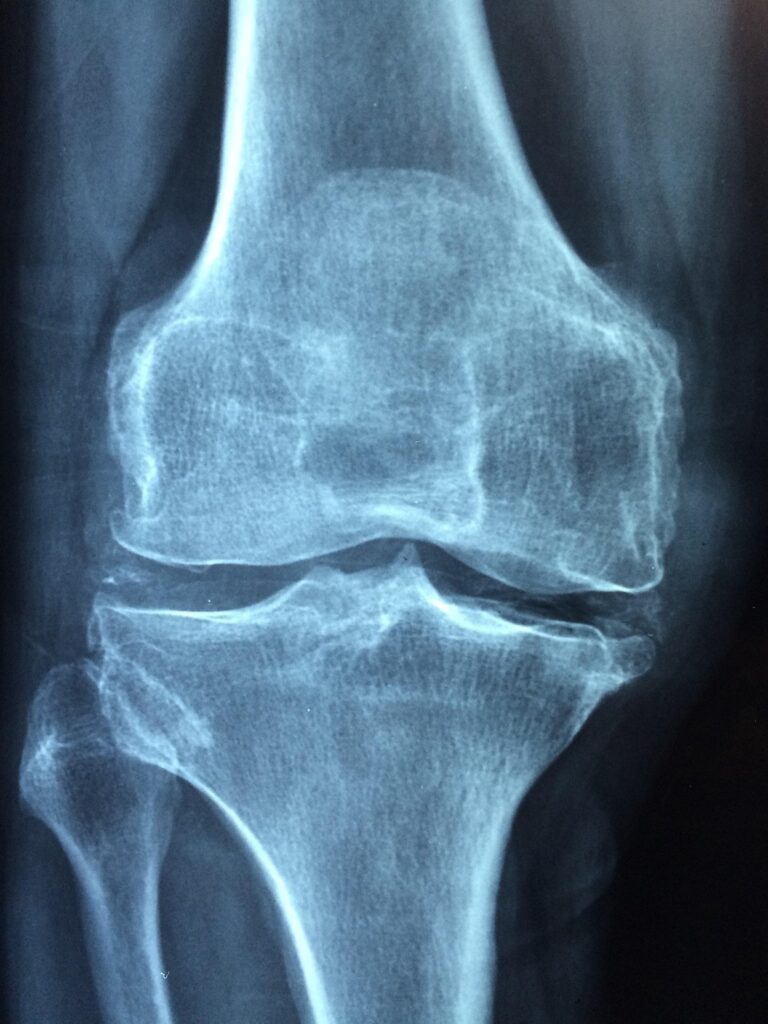

膝痛は、年齢を重ねるにつれて多くの方が経験する問題です。特に、日常生活の中で膝に負担がかかることで痛みが生じることがよくあります。

• 加齢による関節の変化

• 怪我や炎症